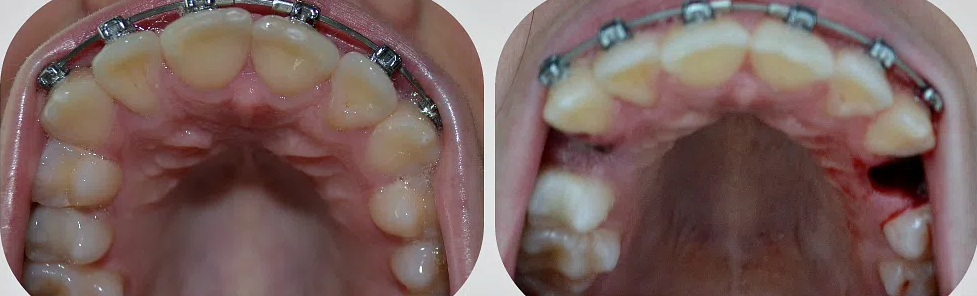

Вырвать зуб: фото до и после

• Проблемы с зубом мудрости.

Если восьмерки неправильно расположены, они не могут нормально прорезаться и доставляют немало проблем. В таком случае остается их удалить.